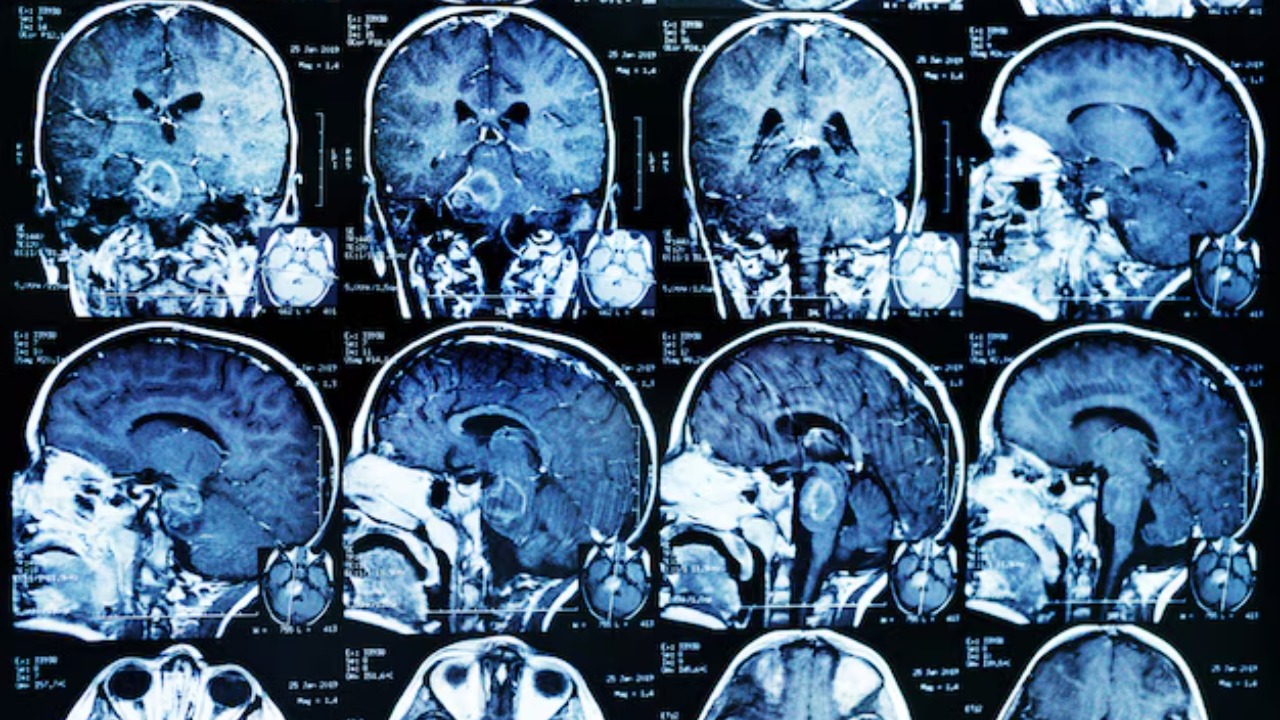

Mini-brains are organoids, essentially simplified versions of an organ produced in vitro in three dimensions that show realistic micro-anatomy. They are derived from human pluripotent stem cells and have been developed to study various aspects of the human brain. The advancements in technology have made it possible to grow these organoids in the lab, enabling scientists to study the brain’s development and function in real-time.

Not only can these mini-brains solve math problems, but they also exhibit similar neural activity to preterm infants. According to a study published in Scientific American, researchers found that the organoids developed complex, organized neural networks. This discovery opens up new possibilities for studying neurodevelopment and neurological disorders.